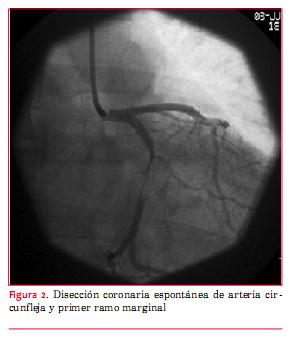

Se envía a centro de hemodinamia de Montevideo, donde arriba ocho horas luego de iniciado el cuadro clínico, con persistencia de los síntomas y de las alteraciones en el ECG. Se realiza coronariografía por acceso radial que muestra disección coronaria espontánea de arteria circunfleja dominante y de primer ramo marginal, con estenosis críticas de ambos vasos (figura 2).